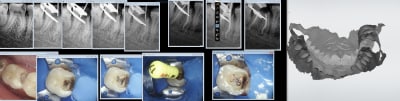

Oui des empreintes turbo. Préprep le temps que l'anesthésie de de 27 et 47 prennent pour les endos. Pour l'empreinte des préparations c'est 15 secondes. -))))

Miam ! Il y a encore de la marge d'efficience sur l'endo. L'obturation conventionnelle à mi canal au lentulo dans la salive.